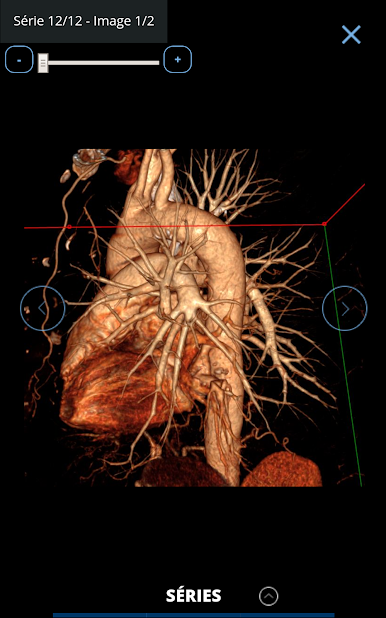

Consultation with images of hundreds of typical and rare cases is simple, all accompanied by explanatory captions and course records. All imaging modalities are represented: CT, MRI, ultrasound, PET-CT scans, interventional radiology angiography.